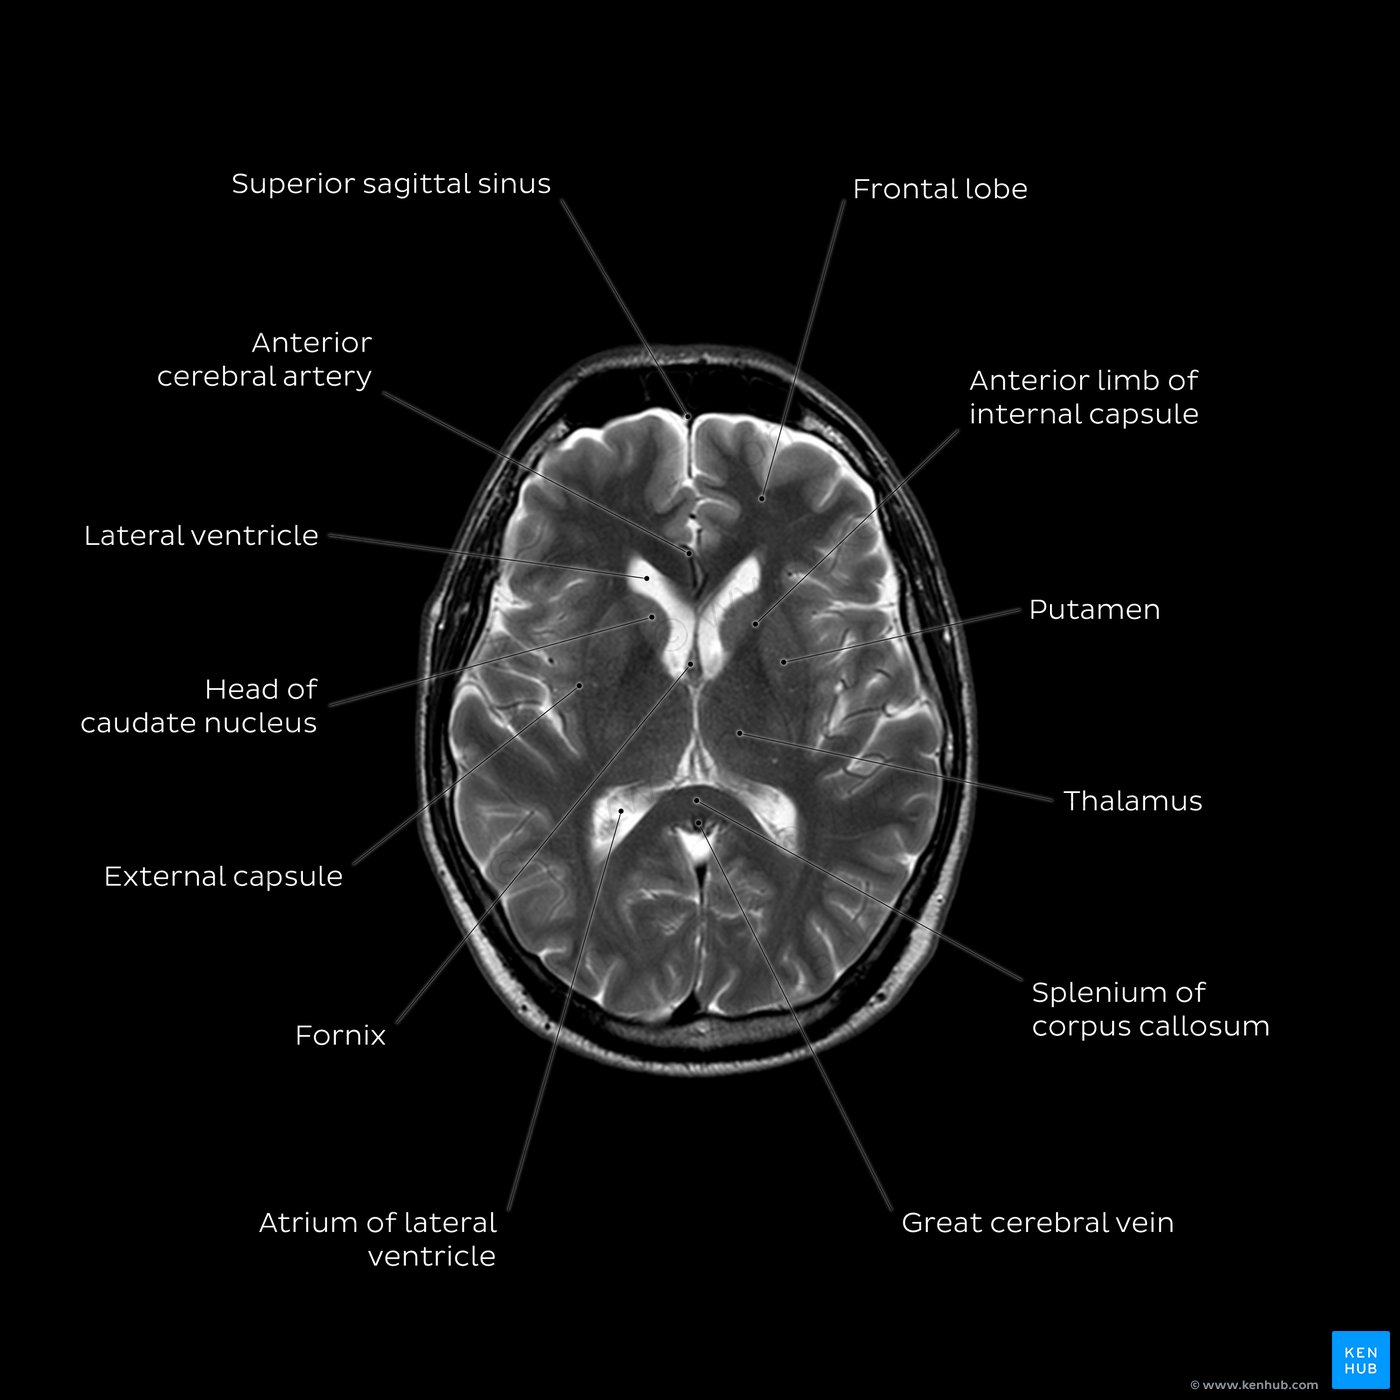

Wondering about the normal temperature for baby? Learn how to accurately measure your infant’s body temperature, identify signs of a fever, and understand when to contact a pediatrician. This guide provides essential insights into managing pediatric health, ensuring you can confidently monitor your child's well-being and recognize when a thermometer reading requires professional medical attention for your newborn.